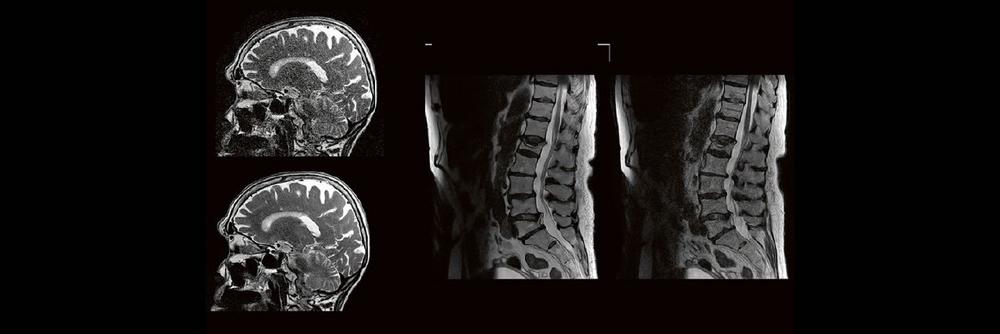

Professor Dr. med. Marc Brockmann WEITERENTWICKLUNGEN VON KOPF BIS FUSS BEIM VC Oberstarzt Dr. med. Stephan Waldeck DEEP-LEARNING-REKONSTRUKTION IN DER NEURORADIOLOGIE Die CT ist ein essentielles Routine-Verfahren in der Neuroradiologie. Bei steigender Bildqualität konnte die Röntgendosis mit neuen Technologien in der letzten Dekade deutlich gesenkt werden, was für die zielgerichtete und möglichst schonende Behandlung von…